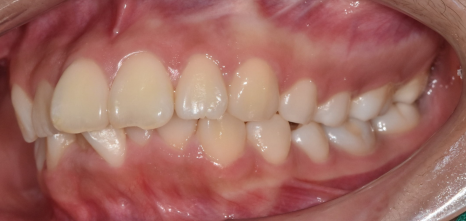

교합 상태, 치아 배열 상태를 확인하기 위해

5분할 포토라 불리는 구강 내 사진을 찍고

뽄도 뜹니다.

교정 모델을 만들기도 하며

이 과정에서 구강 스캐너가 동원되기도 합니다.

앞으로 교정을 통해 치아가 어떻게 움직일지 예측합니다.